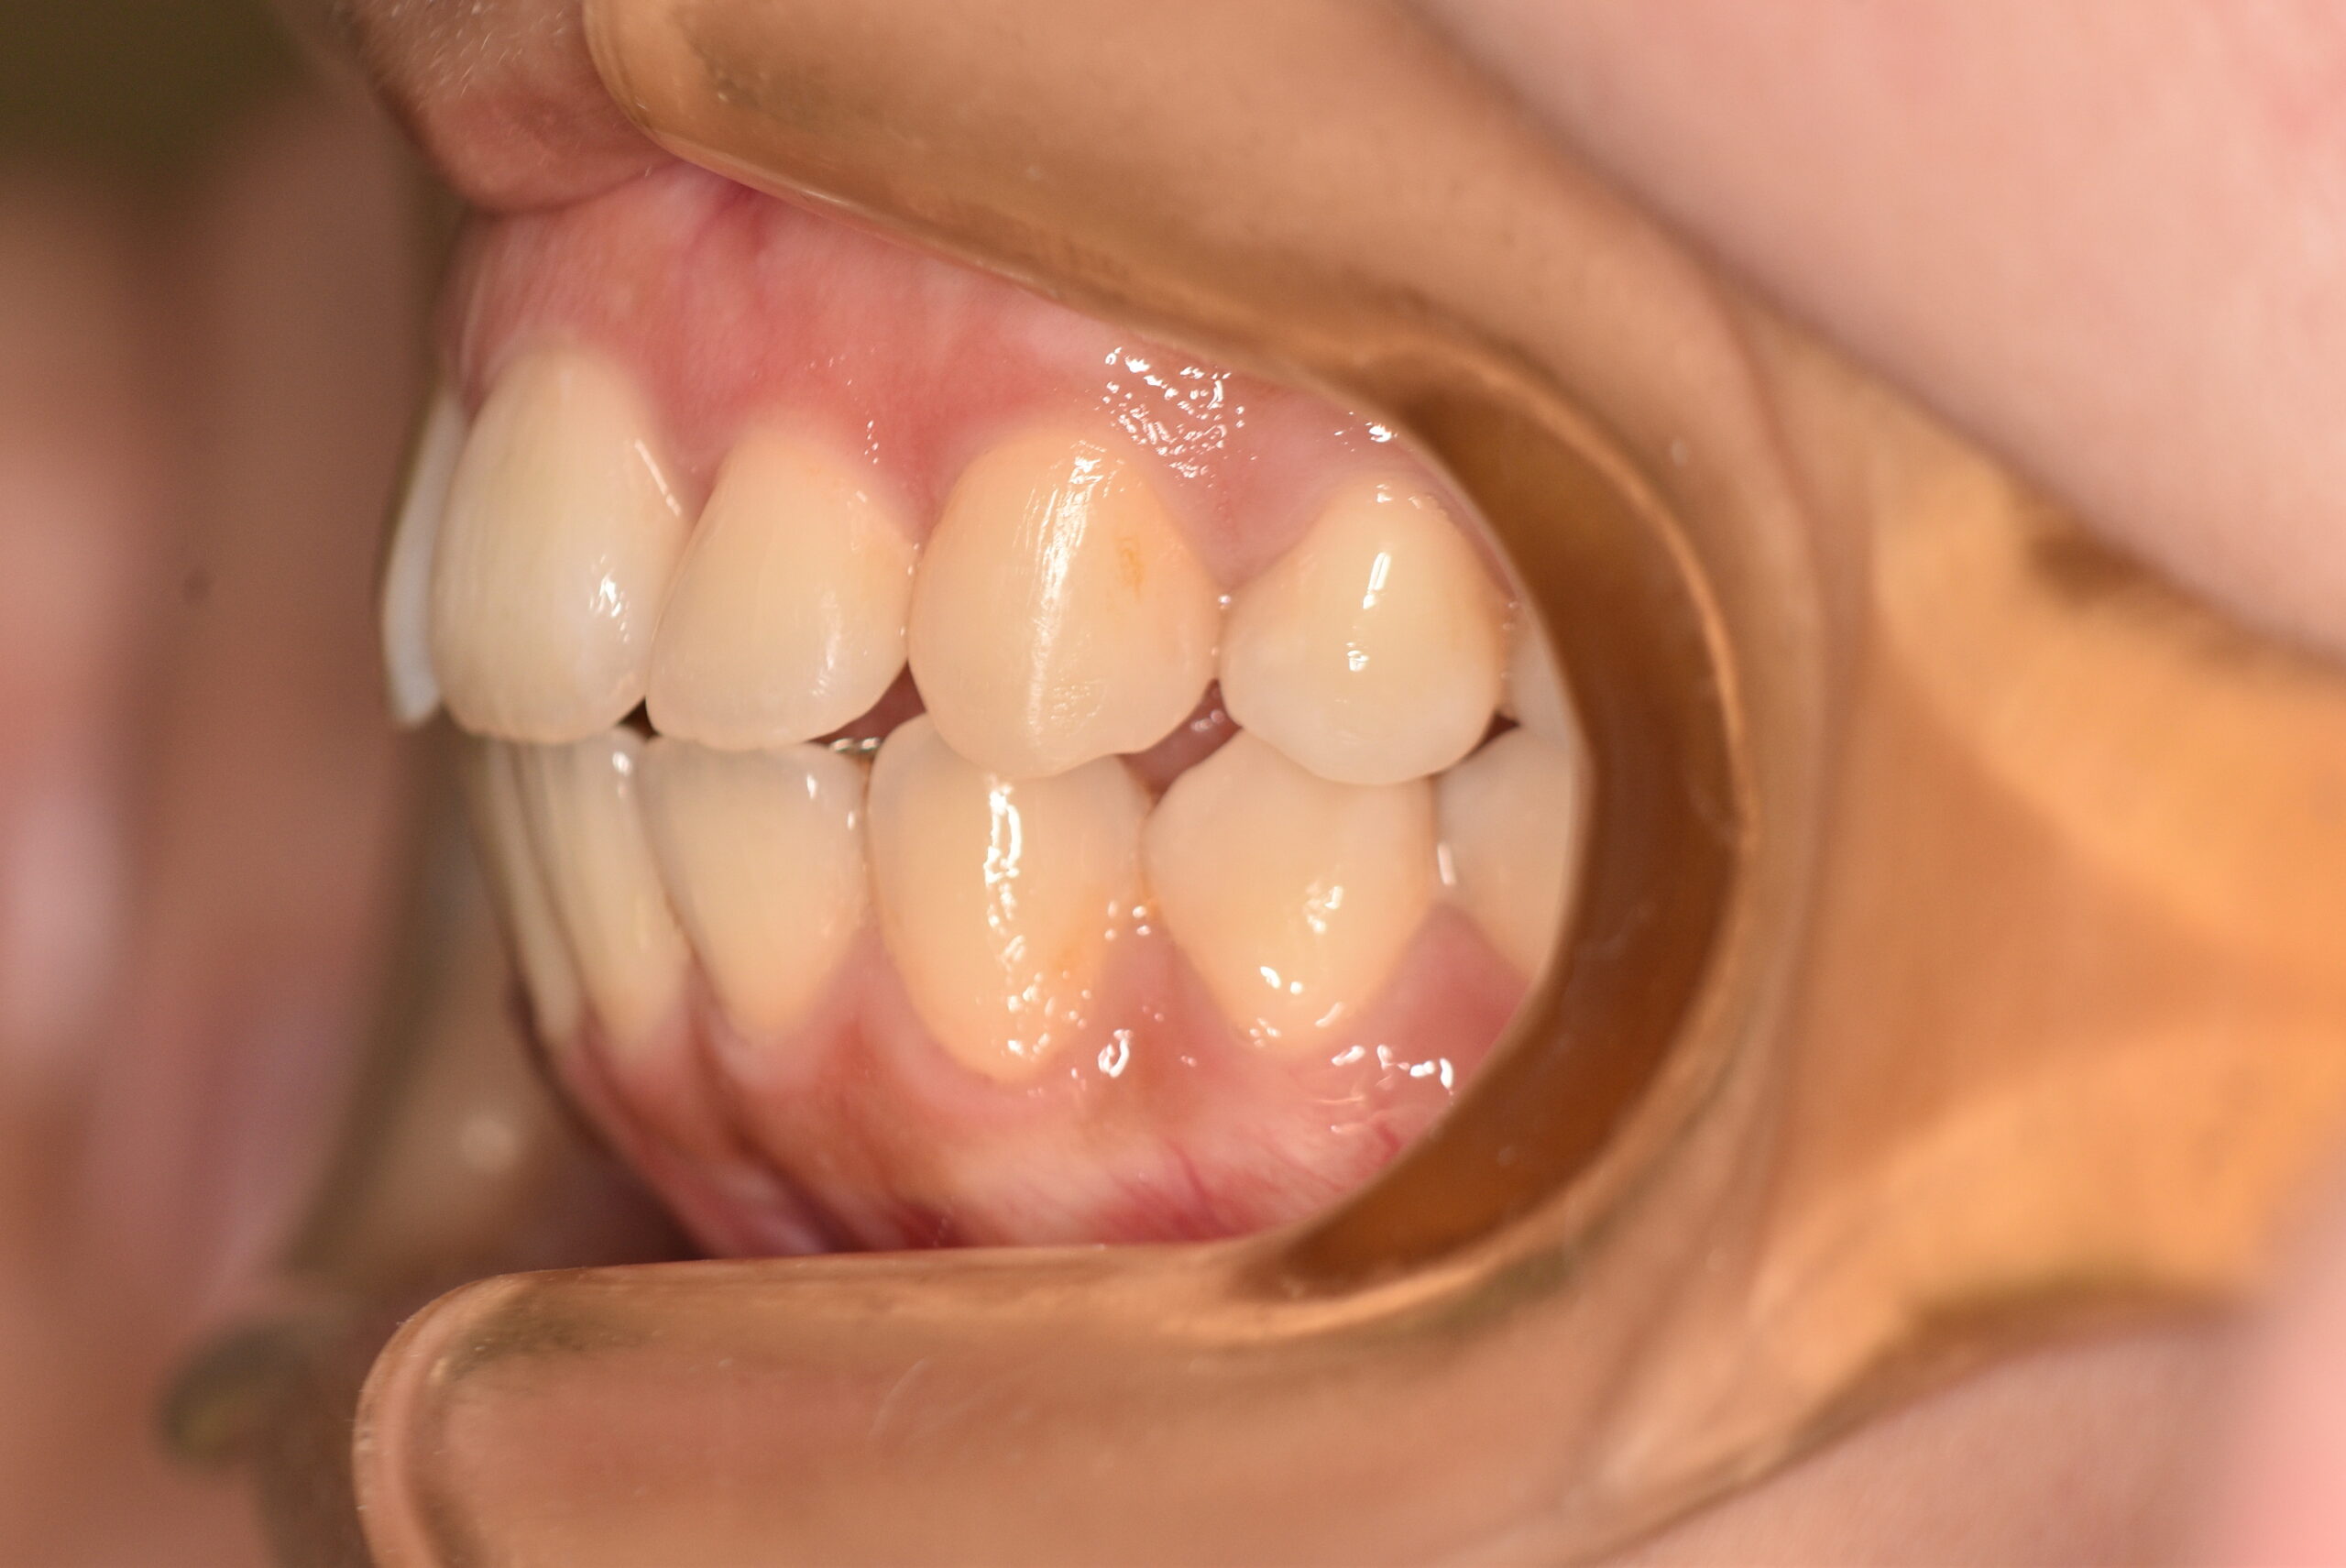

動的治療終了時

症例 症例 症例 症例

治療としては、上顎左右第1小臼歯を抜歯し、セルフライゲーションブラケット装置(デーモンシステム)で歯の配列を行いました。

同時に顎間ゴムにて咬合関係の改善を行いました。

この際、上顎に歯科矯正用アンカースクリューを設置し上顎前歯部後退時の土台としました。

治療期間は、2年11ヶ月でした。